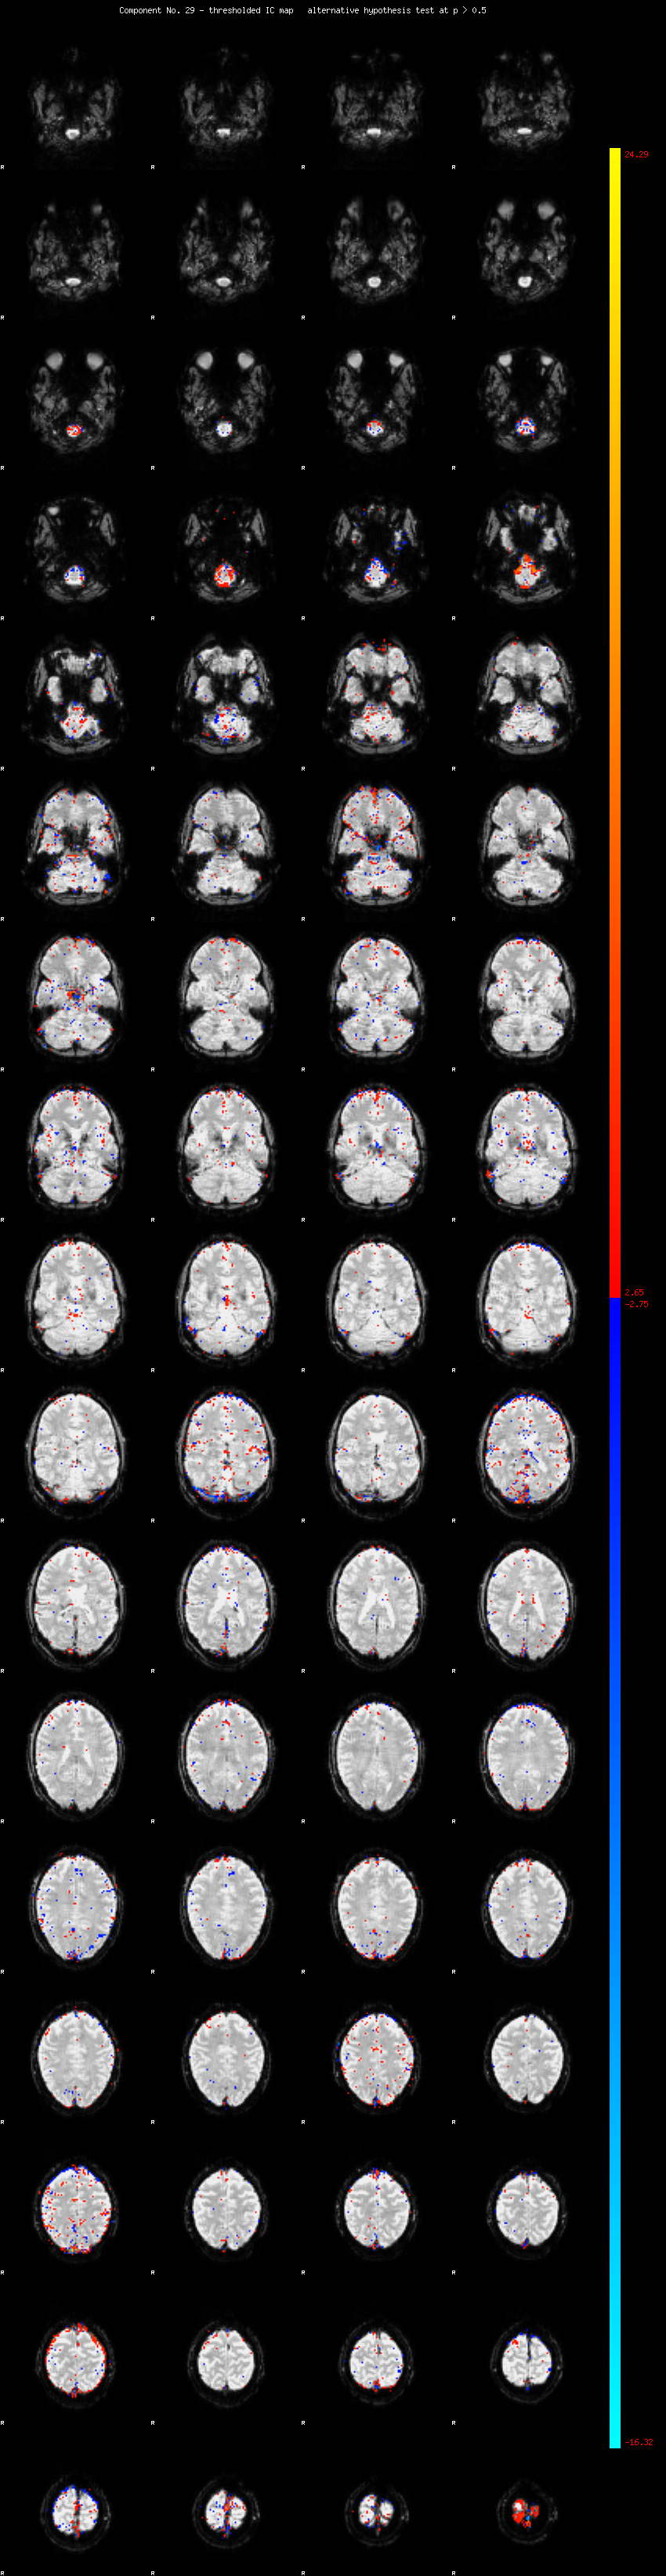

MELODIC Component 29

1.24 % of explained variance;     0.82 % of total variance